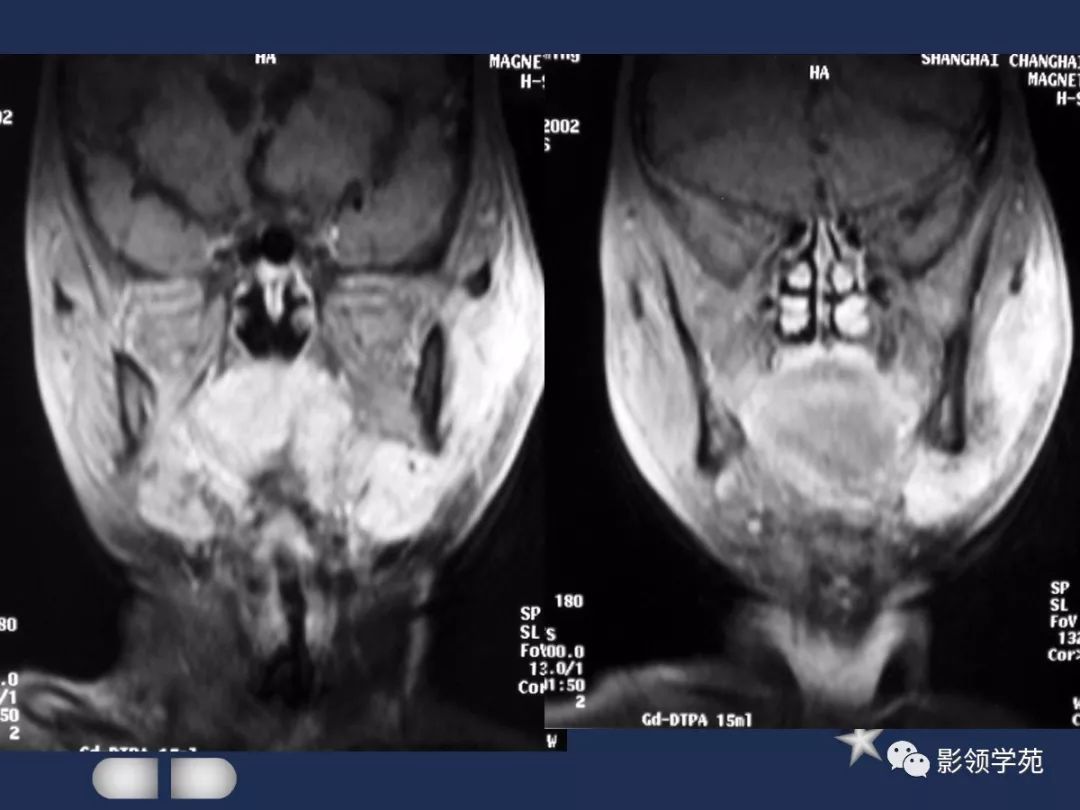

MRI表现

- MRI上实性肿块在T1WI上呈等低信号,在T2WI上呈高信号,囊变区呈长T1长T2信号,钙化在T1WI及T2WI上均呈低信号。